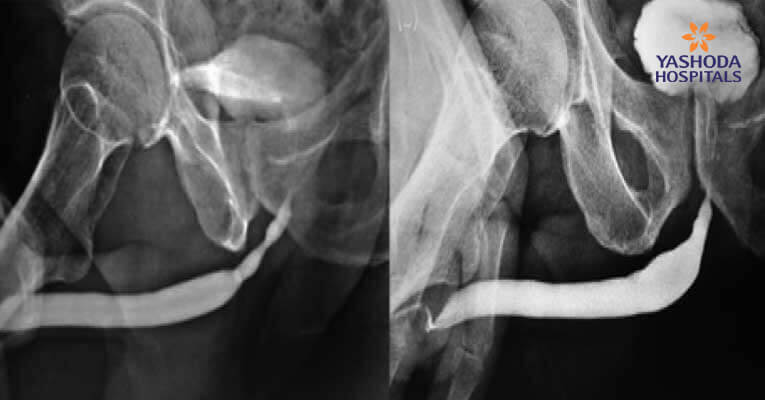

Ovarian vein coil embolization for pelvic congestion syndrome

Background A 27-year-old female presented with complaints of chronic severe lower abdominal pain. Diagnosis & Treatment The USG and Doppler images demonstrated pelvic varicosities. The DSA image demonstrated dilated left ovarian vein with reflux into pelvic...